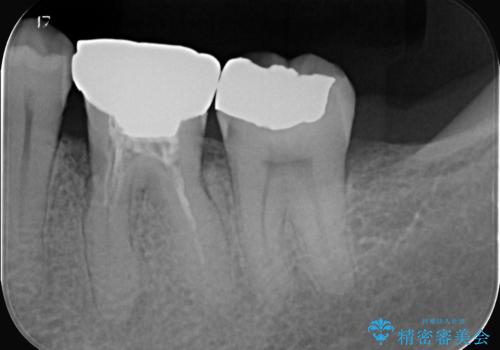

- お口の中にある銀歯を全てなくして、白く健康的な状態にしたい」という主訴でご来院されました。長年使用してきた複数の銀歯は、経年劣化により適合が悪くなっており、一部では内部で二次カリエス(虫歯の再発)も認められました。

銀歯の除去と精密な再治療: 古い銀歯を一つひとつ丁寧に取り外し、内部の虫歯を徹底的に除去。神経を保護するための処置を行った上で、適合性を極限まで高めるために精密な型取りを行いました。

オールセラミックによる修復: 天然歯のような光の透過性と硬さを持つオールセラミックを使用しました。奥歯であっても、患者様固有の歯の色調や咬み合わせの溝を忠実に再現した修復物を装着。金属を一切使用しないことで、金属アレルギーのリスクを排除し、歯肉の色が黒ずむ心配もなくなりました。